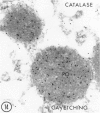

The immunocytochemical localization of catalase and three enzymes of the peroxisomal lipid beta-oxidation system--acyl-CoA oxidase, the bifunctional protein enoyl-CoA hydratase, 3-hydroxyacyl-CoA dehydrogenase, and 3-ketoacyl-CoA thiolase--in human liver biopsies was investigated by means of light and electron microscopy. The antisera raised against all four enzymes from rat liver cross-reacted with the corresponding proteins in homogenates of human liver as revealed by immunoblotting. For light-microscopic localization in glutaraldehyde-fixed Epon-embedded material, the removal of resin and controlled digestion with trypsin was necessary. At the ultrastructural level specific labeling for all four antigens was found by the protein A-gold technique in peroxisomes of liver parenchymal cells fixed with formaldehyde-low glutaraldehyde concentrations and embedded in Lowicryl K4M. In biopsies fixed with glutaraldehyde and embedded in Epon, treatment with metaperiodate or etching with sodium ethoxide improved the immunolabeling. After such treatment catalase showed the most intense labeling and acyl-CoA oxidase the weakest, the two other proteins exhibiting an intermediate immunoreaction. In material postfixed with osmium only catalase could be visualized in peroxisomes. The immunocytochemical investigation of peroxisomal proteins in human liver biopsies provides a simple and highly promising approach for further elucidation of the pathophysiology of peroxisomal disorders.